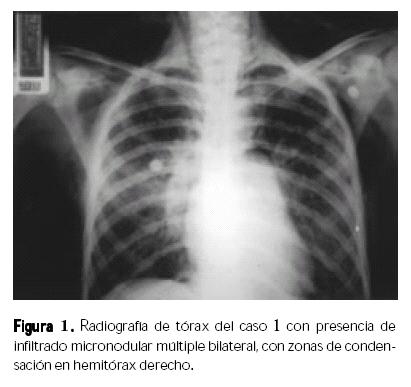

Caso 1. Femenino de 15 años de edad con infección por VIH/SIDA, recibió tratamiento antirretroviral por más de un año con esquema cuádruple con un inhibidor de proteasa (nelfinavir), un análogo no nucleósido (efavirenz) y dos análogos nucleósidos (d4T, 3TC). Se mantuvo con carga viral indetectable, tenía cinco meses de haber suspendido en forma definitiva el tratamiento por decisión propia. Inició con fiebre intermitente de tres semanas de evolución, malestar general, crecimiento ganglionar cervical, tos, disnea y hepatomegalia. Al ingreso tenía 99 células/µL de CD4 y carga viral mayor a 75 000 copias/mL, radiografía de tórax con infiltrado micronodular múltiple bilateral, con zonas de condensación en hemitórax derecho (Fig. 1); biometría hemática con hemoglobina de 8.5 g/dL, plaquetas de 99 000/mm3; baciloscopias negativas para Mycobacterium tuberculosis y PPD negativo. Ingresó al Servicio de Infectología con diagnóstico de neumonía de focos múltiples. Se le inició tratamiento con vancomicina, ceftazidima y trimetoprim–sulfametoxazol; presentó mala evolución. Requirió ventilación mecánica y se trasladó a terapia intensiva pediátrica. El cultivo de aspirado bronquioalveolar reportó crecimiento de H. capsulatum (al séptimo día de tratamiento), por lo que se le inició anfotericina B sin mejoría clínica; falleció cuatro días después.